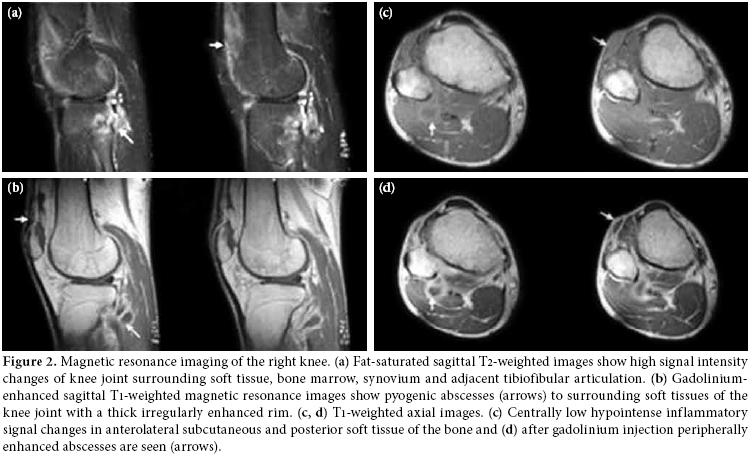

Consolidation and irregular cavitation in the upper zone of the left lung was detected in the chest radiograph (Figure 1); however, knee radiographs were considered normal. Magnetic resonance imaging of the right knee revealed inflammation in the knee, around the joint and in the superior tibiofibular articulation. The knee MRI also revealed centrally necrotic abscesses with peripheral enhancement of the rim after a gadolinium injection (Figure 2). An MRI of the right shoulder also showed increased inflammatory signal changes in the acromioclavicular joint and adjacent soft tissue with enhancement after gadolinium injection (Figure 3). The purified protein derivative (PPD) skin test for Tbc measured 22 mm. A synovial biopsy taken from the knee detected granulomatous inflammation with caseation necrosis. Antibiotic treatment with isoniazid, rifampicin, ethambutol and pyrazinamide were prescribed for two months followed by rifampicin and isoniazid for seven months. The patient showed significant improvement in the knee and shoulder within two months and close to complete improvement within six months.

Magnetic resonance imaging is the best modality to evaluate soft tissue affection by demonstrating marrow changes, joint effusion, synovitis, pannus, and cartilage and bone erosions.[2,16] Joint and periarticular involvement and lesions are particularly well defined by an MRI. The definitive diagnosis is performed from a positive mycobacterial culture and a histological examination of synovial fluid or synovial membranes. An examination of a biopsy specimen is an important and useful diagnostic method. Amplifying DNA of Mycobacterium tuberculosis from synovial fluid or bone by PCR could be useful for the early diagnosis of Tbc. We performed a definitive diagnosis through the histopathological examination of a synovial biopsy, a chest radiograph showing cavitation and the definitive demonstration on MRI examination. This was done in spite of the lack of positivity of mycobacterial culture and PCR. In addition, following the initiation of specific antituberculous treatment, the patient showed significant improvement in the knee and shoulder within two months with close to complete improvement within six months. We extended treatment to nine months in accordance with the recommendations for musculoskeletal tuberculosis in the literature and by the Turkey Ministry of Health.[17,18]